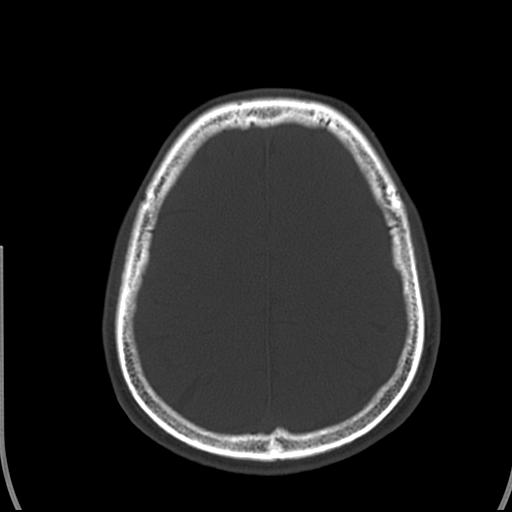

标题: CT25435:头皮下高密度影???

头皮下高密度结节影???临床上在老年男性比较常见。大家看看是什么?成因是? 本例患者,男性,51岁。外伤来诊。无染发史及发根植入史。